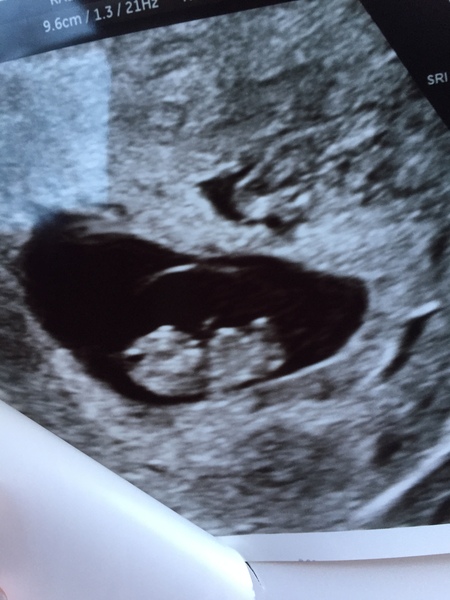

Largemelons · 29/12/2016 14:55

Had a lovely early scan today! All is good, measuring 8+5 due date 5th August! Feeling very relieved and happy.